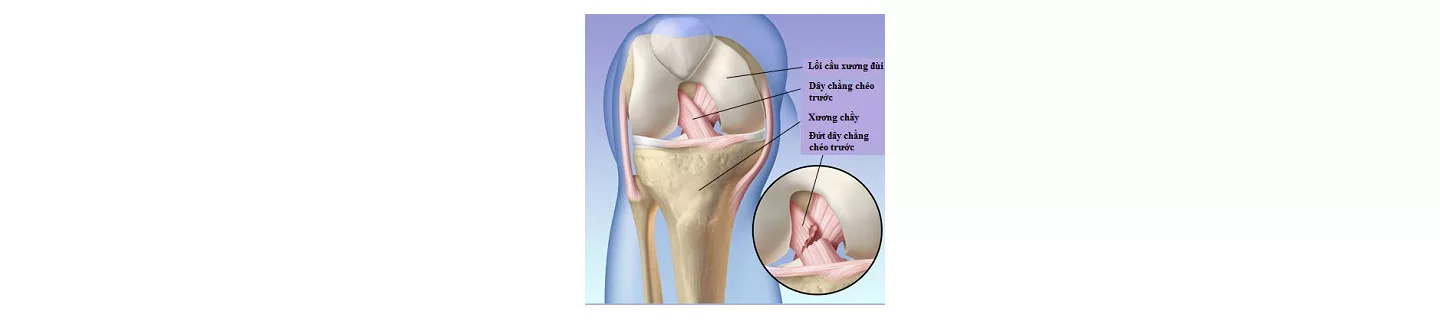

Rách dây chằng chéo trước

Dây chằng chéo trước giúp giữ và ổn định khớp gối. Nếu đặt chân xuống sàn sai tư thế, đổi hướng quá nhanh hoặc dừng lại đột ngột (chẳng hạn khi chơi bóng đá), bạn có thể bị rách dây chằng chéo trước. Một số triệu chứng của tình trạng này là sưng đau, hạn chế vận động, đi lại khó khăn. Rách dây chằng chéo trước thường cần phải phẫu thuật nội soi khớp để tái tạo dây chằng và tập vật lý trị liệu. Nếu bạn không có chỉ định phẫu thuật thì vật lý trị liệu và đeo băng ép có thể giúp bạn cảm thấy dễ chịu nhưng sẽ không giải quyết được vấn đề.